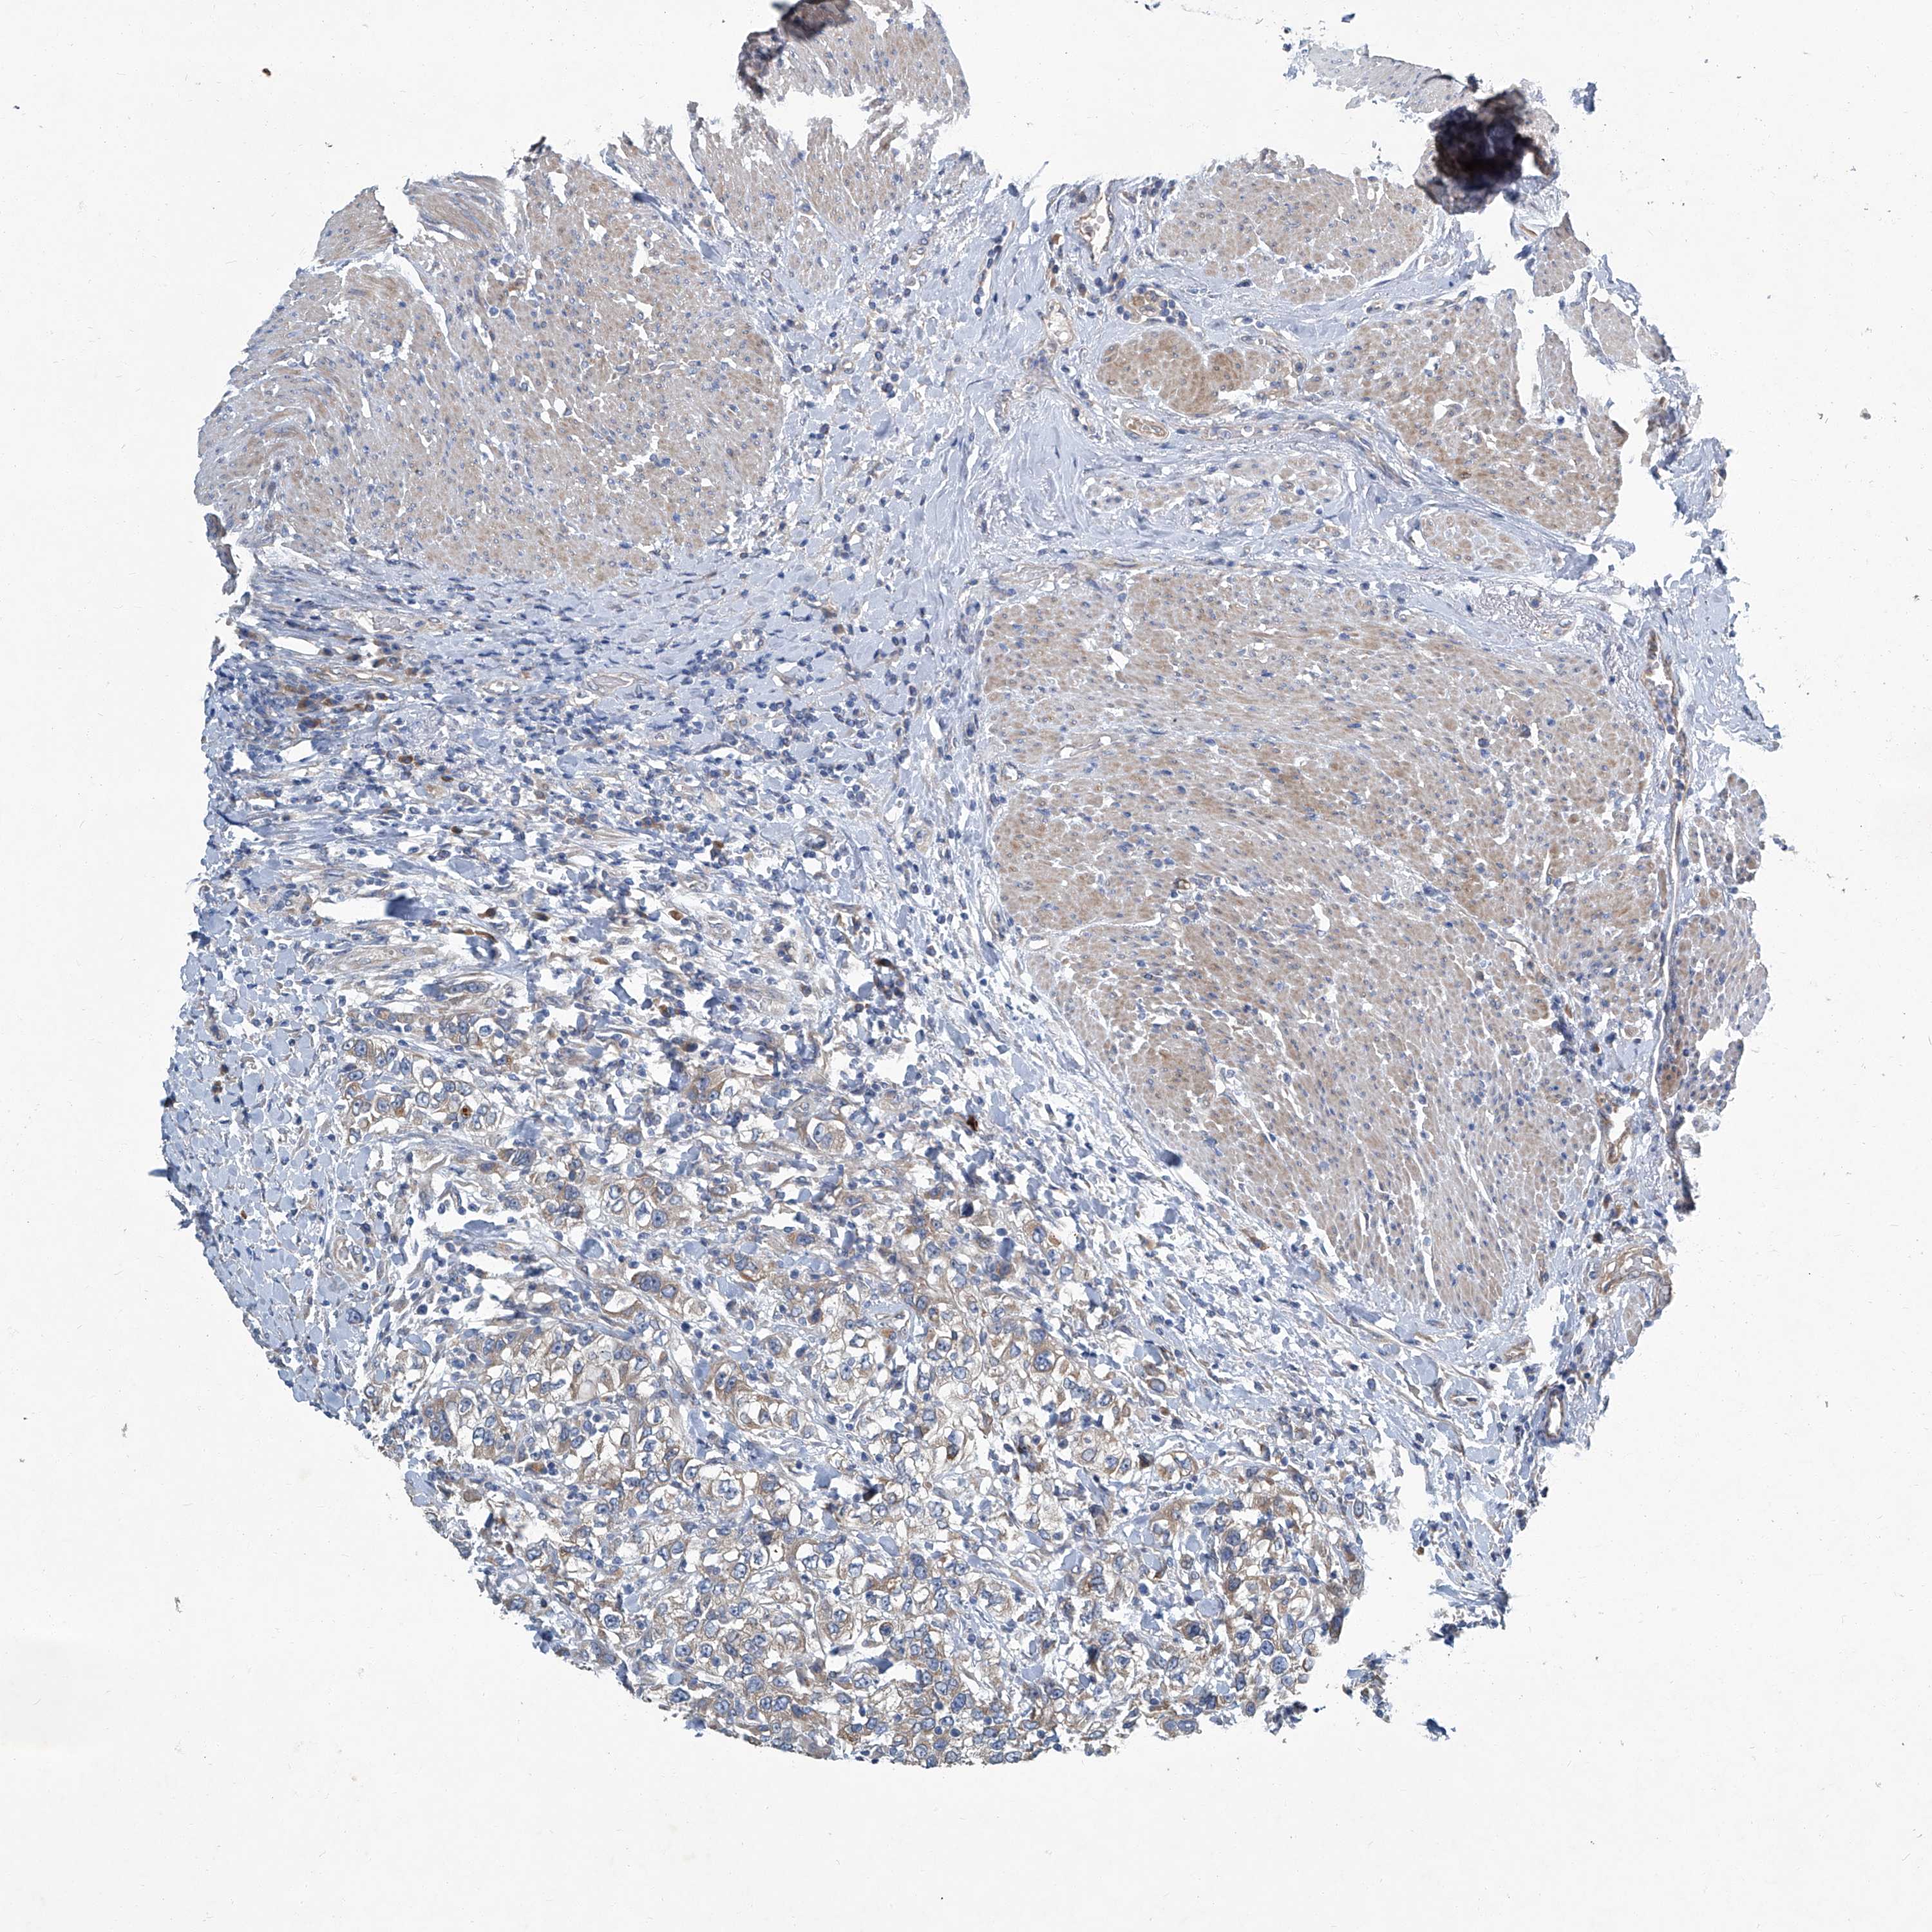

UROTHELIAL CANCER - Protein expressioni

A mouse-over function shows sample information and annotation data. Click on an image to view it in a full screen mode. Samples can be filtered based on level of antibody staining by selecting one or several of the following categories: high, medium, low and not detected. The assay and annotation is described here.

Note that samples used for immunohistochemistry by the Human Protein Atlas do not correspond to samples in the TCGA dataset.

Antibody stainingi

Antibody staining in the annotated cell types in the current human tissue is reported as not detected, low, medium, or high, based on conventional immunohistochemistry profiling in selected tissues. This score is based on the combination of the staining intensity and fraction of stained cells.

Each image is clickable and will lead to virtual microscopy that enables deeper exploration of all samples and also displays staining intensity scores, fraction scores and subcellular localization as well as patient and tissue information for each sample.

Antibody HPA029893

Staining

High

Medium

Low

Not detected

Intensity

Strong

Moderate

Weak

Negative

Quantity

>75%

75%-25%

<25%

None

Location

Nuclear

Cytoplasmic/membranous

Cytoplasmic/membranous,nuclear

Urothelial carcinoma, Low grade

Urothelial carcinoma, High grade